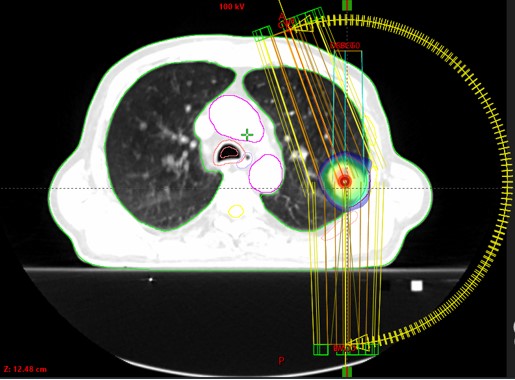

Bolesnik, rođ. 1948.

Dijagnoza:

Neoplasma lobi superioris pulmonis sinistri (12/2021)

PHD: Adenocarcinoma

SABR propter neopl. pulm. sin. (2/2022)

Rezultat – 4 mjeseca nakon RK

Smanjenje tumora za 80%